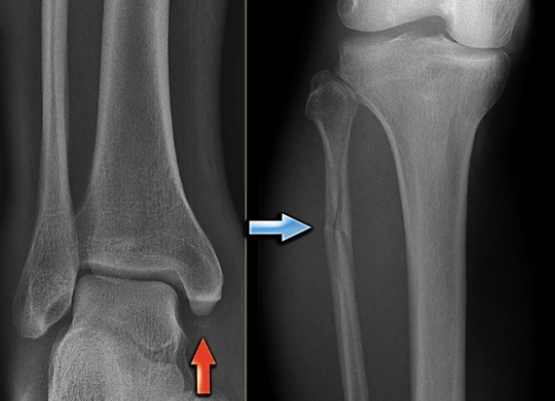

很多人一聽到骨裂就以為是輕微骨折,但其實骨裂是骨折的一種形式,指的是骨頭出現裂縫但沒有完全斷開。這種傷勢通常沒那麼嚴重,但如果不處理好,還是會拖很久。骨裂多久會好,首先得看你是哪種骨裂。常見的像是應力性骨裂,這通常發生在運動員身上,因為重複性壓力導致骨頭出現細微裂縫。另一種是創傷性骨裂,比如車禍或跌倒造成的。

- 就醫診斷:X光或MRI檢查確認骨裂程度。